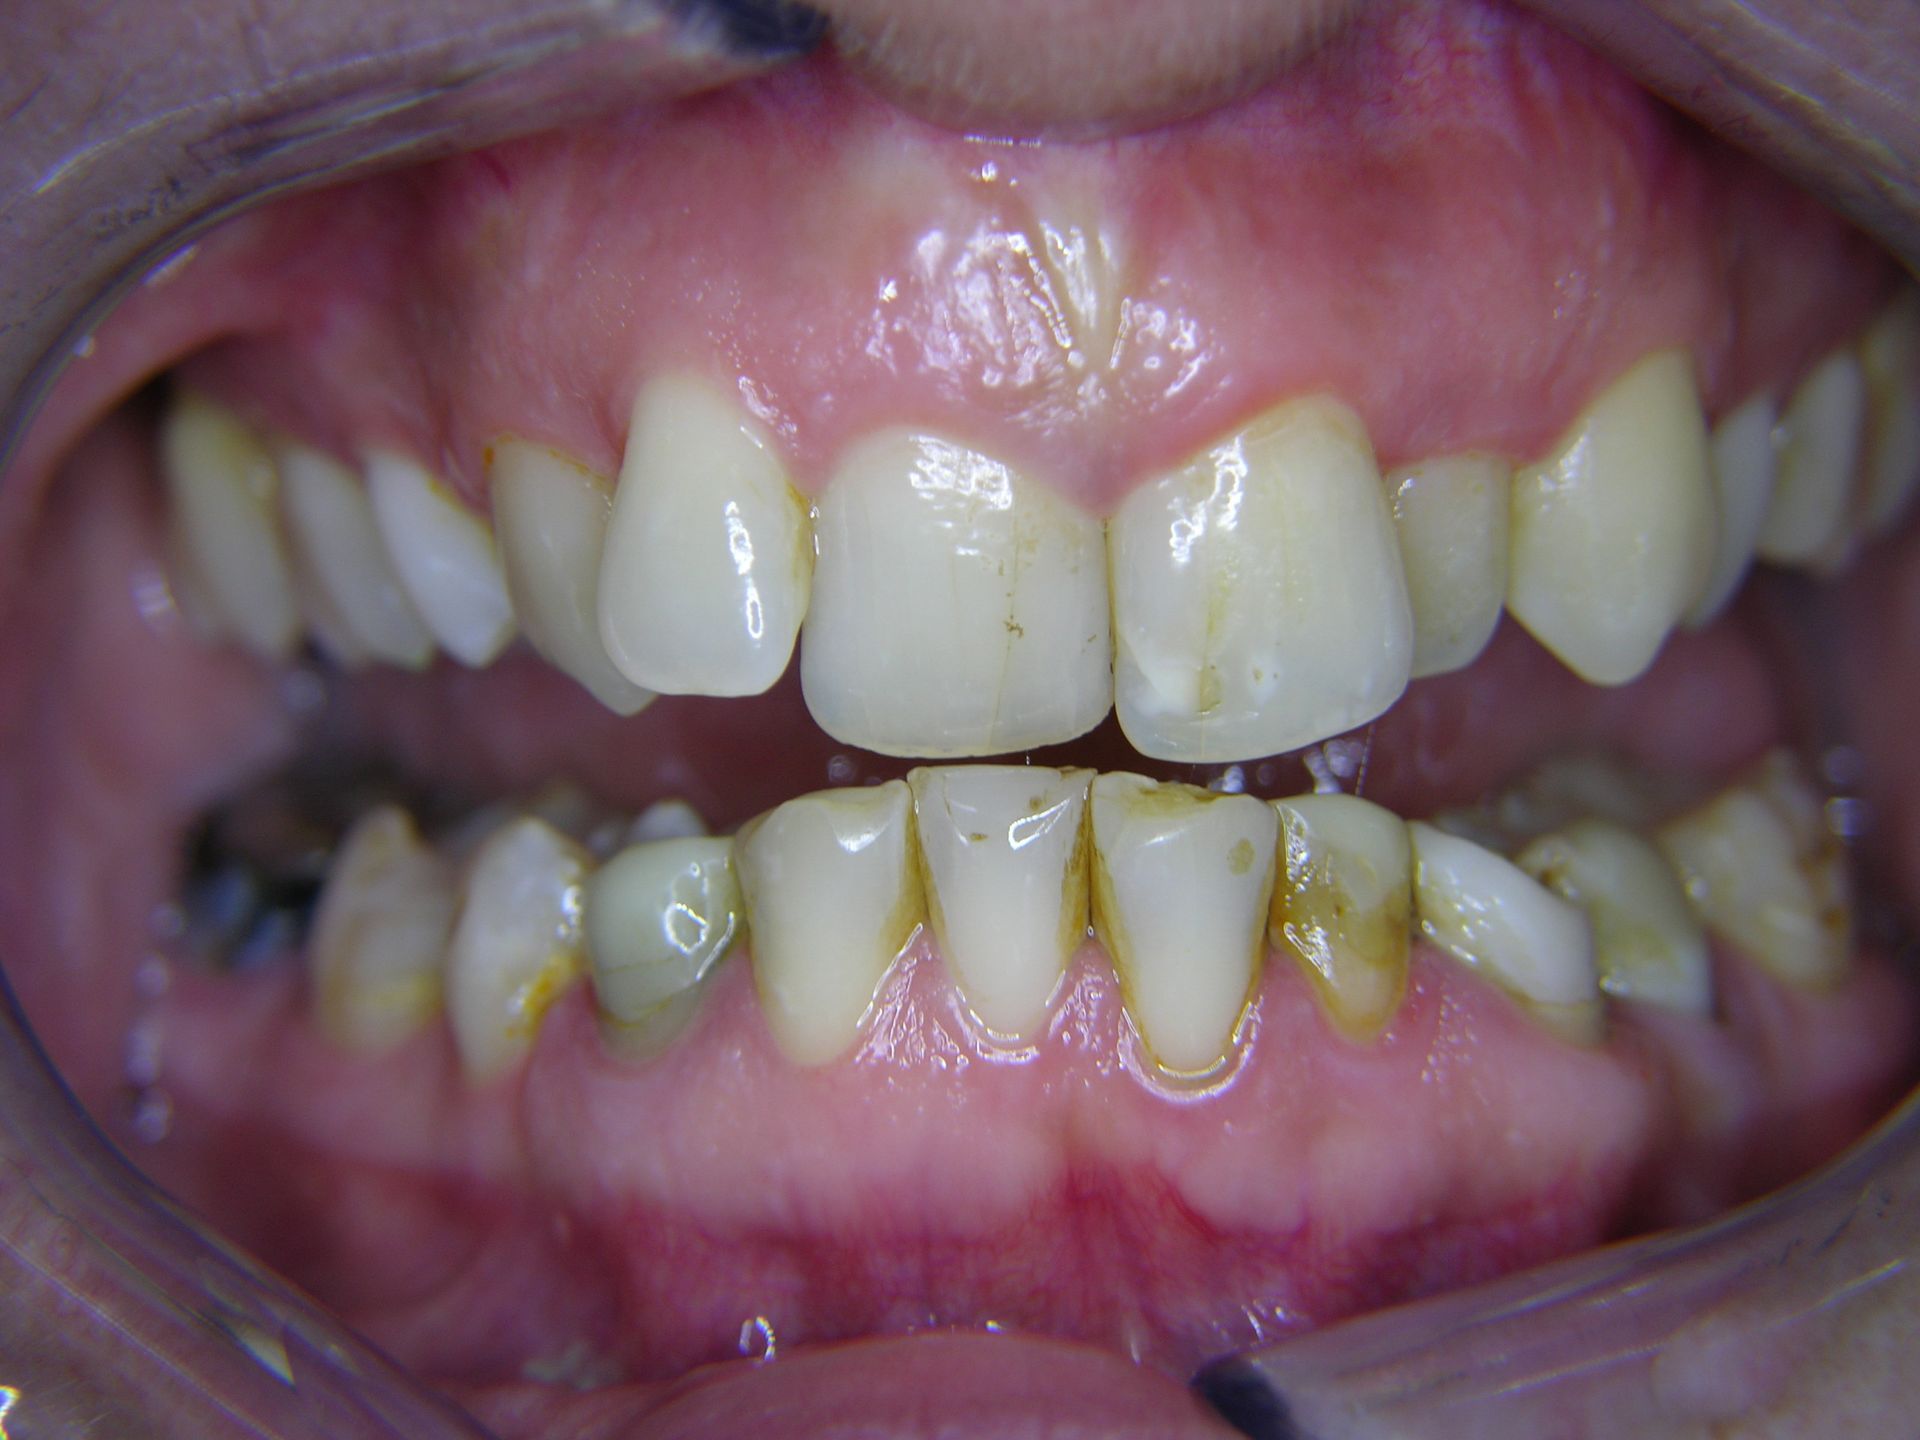

Beispiele von Versorgungen